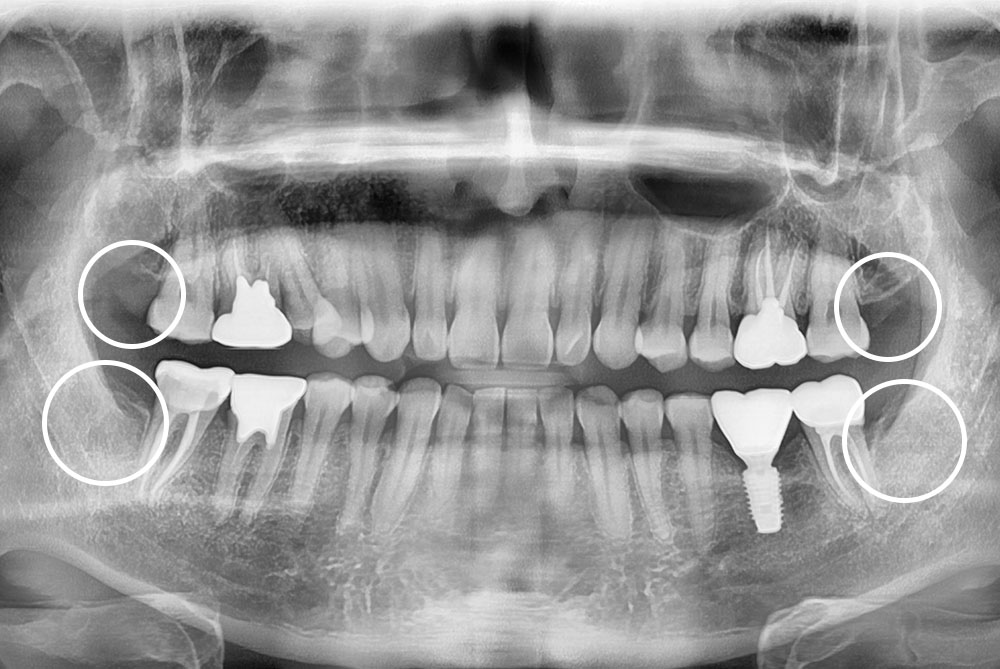

[사랑니] 매복 사랑니 발치

df7ba99fa5f4d1c1ee6a7442f043b59c.jpg

치료전 : 2019-05-23